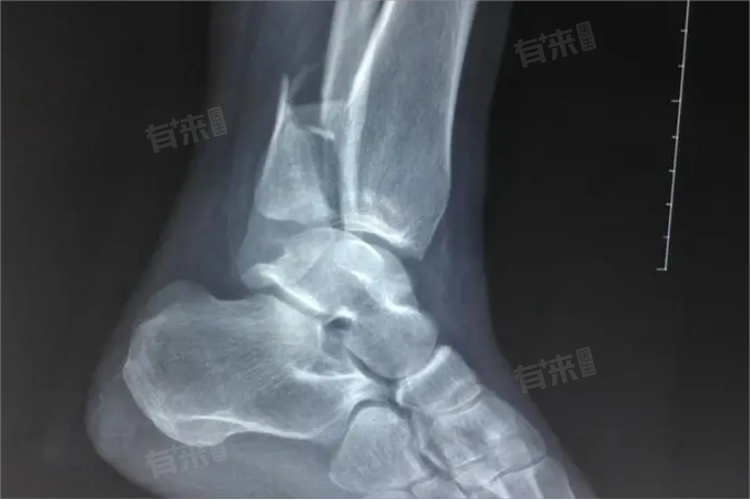

脚腕骨折原因包括外力作用、骨质疏松等,患者需要及时就医,并在医生指导下采取保守治疗、手术治疗等措施,以促使局部组织修复。

- 手术治疗:如果骨折移位明显、手法复位失败或伴有神经、血管损伤等情况,通常需要进行手术治疗。手术的目的是恢复骨折的正常解剖位置,固定骨折端,促进骨折的愈合。